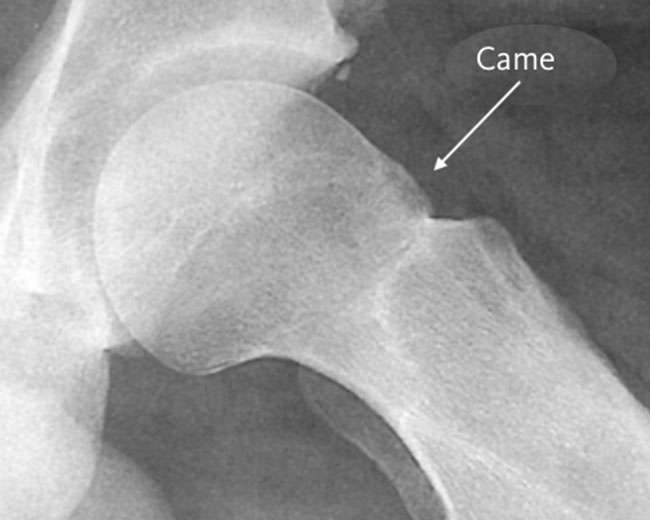

- 1. Le conflit de type CAM (a): excès d'os de la tête et le col fémoral => pas parfaitement ronds